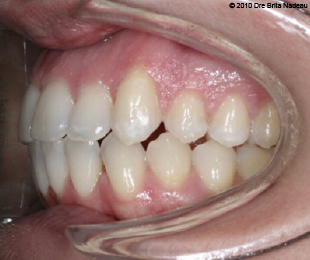

Marie-Hélène Cyr - Left lateral intraoral view - After orthodontic treatments and orthognathic surgeries (January 29, 2010)

January 29, 2010 - My final class I occlusion contrasts with the 2005 left lateral view.